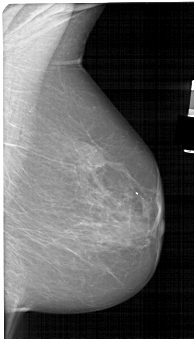

A_1565_1.RIGHT_CC

RIGHT_CC LINES 5491 PIXELS_PER_LINE 3076 BITS_PER_PIXEL 12 RESOLUTION 43.5 NON_OVERLAY